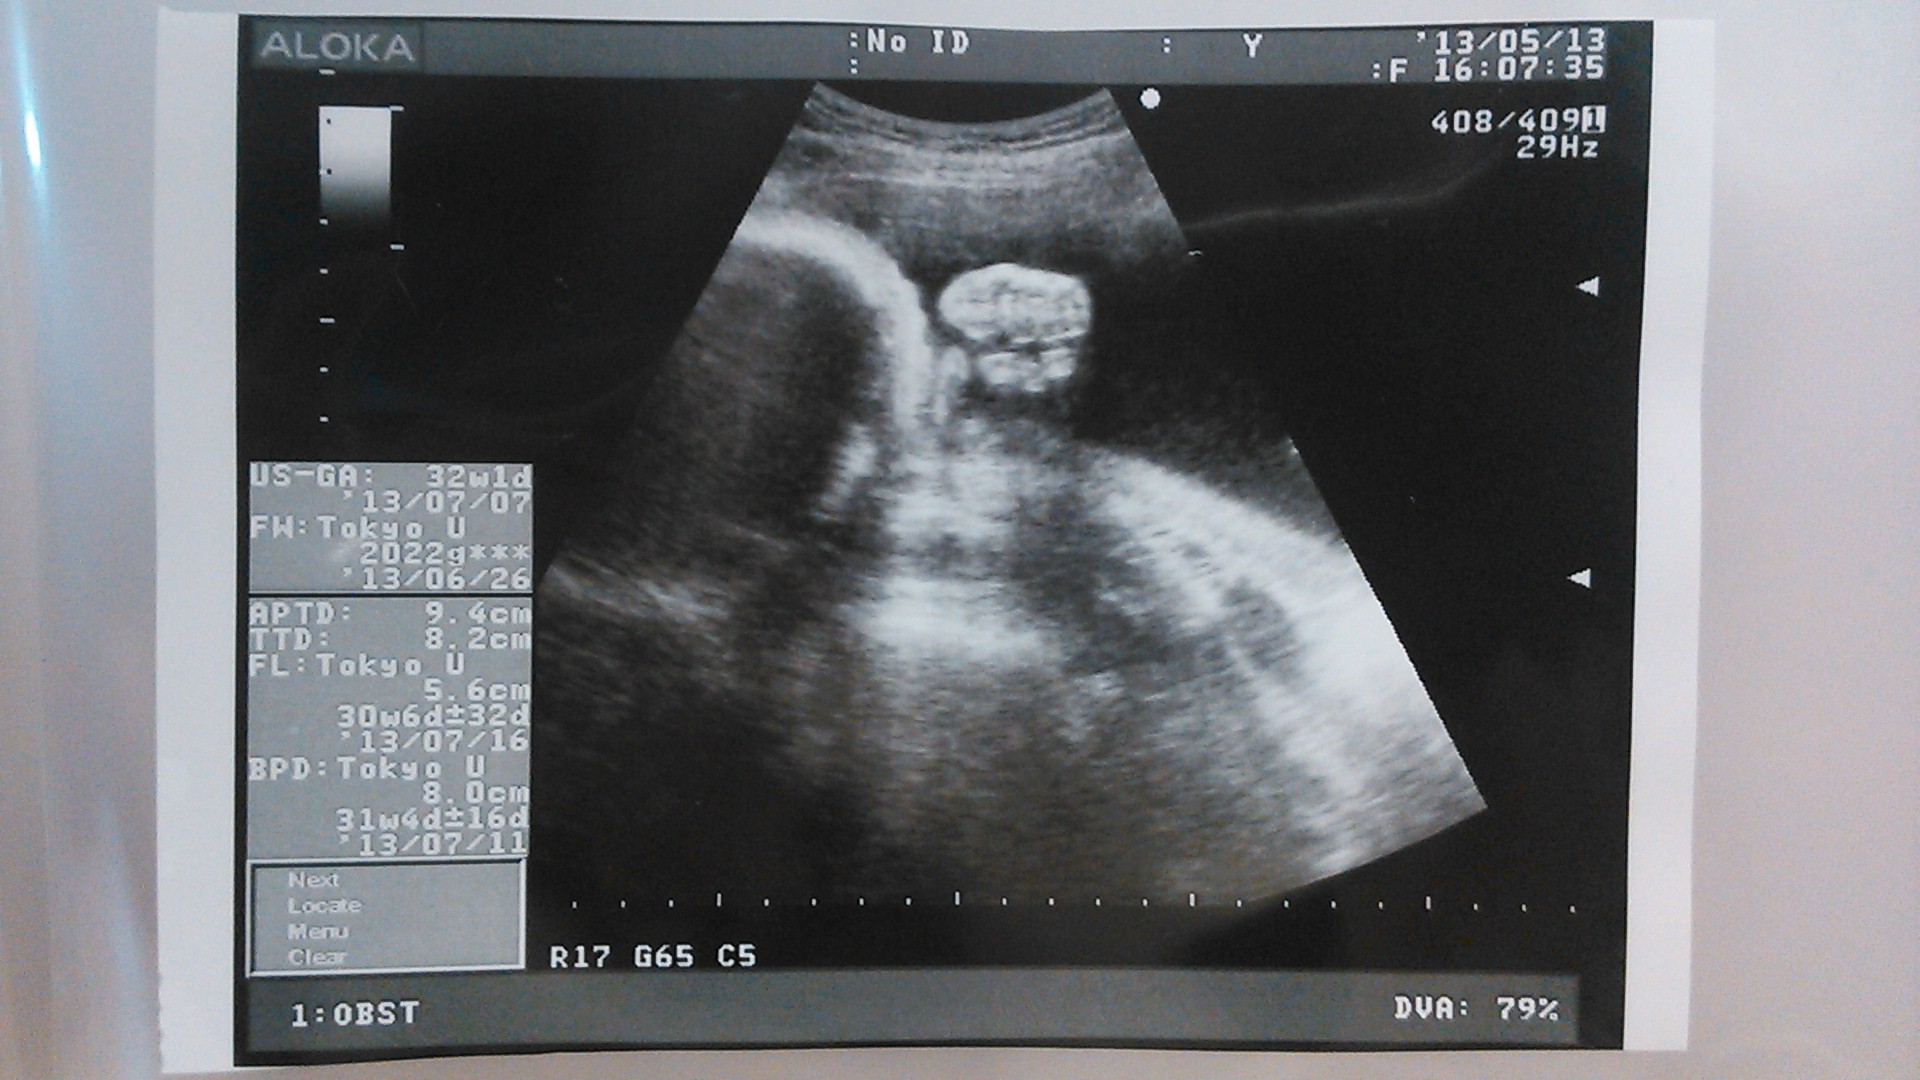

echo